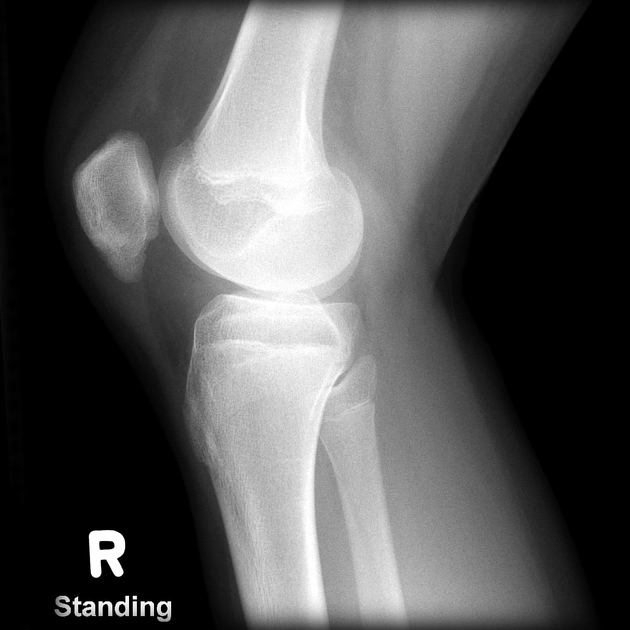

• Gãy bong khớp gối

Gãy Segond (Gãy bong mâm chày do đứt ACL)